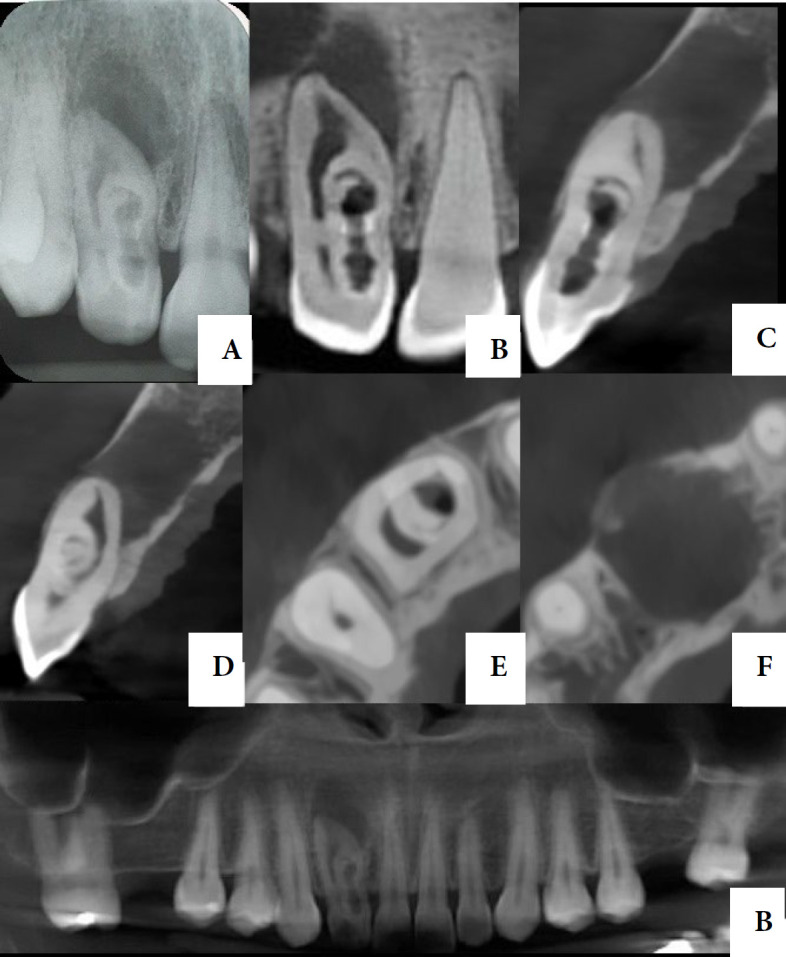

Dens invaginatus (DI) is one of the developmental dental anomalies that results in an invagination of the enamel organ into the dental papila during odontogenesis. The purpose of this study is to report a case of nonsurgical endodontic treatment of an Oehlers type II DI in a right maxillary lateral incisor with an extensive periapical damage, along with the two-year clinical and tomographic follow-up. A 30-year-old patient was referred for endodontic treatment of tooth #12. On clinical examination, a change in the shape and color of the crown was observed. The tooth responded negative to pulp sensibility, percussion, palpation and mobility tests. After tomographic evaluation, an Oehlers type II DI was visualized, in addition to an extensive periradicular lesion. The diagnosis was asymptomatic apical periodontitis. The treatment was carried out in two sessions, through intense enhancement of the auxiliary chemical substance with passive ultrasonic irrigation, XP-Endo Finisher and the use of hydroxide-based intracanal medication. Appropriate treatment in cases with anatomic variations requires an accurate and early diagnosis based on clinical examination and radiographic images. A two-year follow-up of the present case showed that the correct diagnosis associated with appropriate instrumentation techniques, supplementary disinfection, and adequate three-dimensional sealing of the canal with filling material, resulted in regression of the periradicular lesion and bone repair.